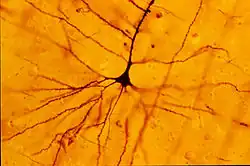

About a decade after Broca's area was recognized as a movement control area of the brain, Vladimir Betz used a new technique, the Golgi stain, to identify a type of giant pyramidal shaped cells that are movement control cells of the brain. These "Betz cells" are among the largest neurons of the human brain and they are depleted from the brains of patients with Lou Gehrig's disease.